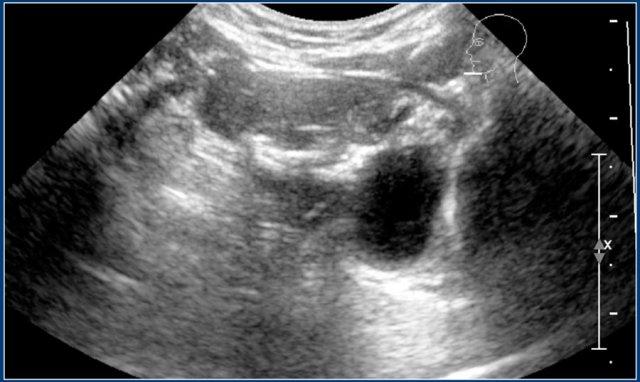

Đây là hình ảnh siêu âm của một u mạch bạch huyết điển hình.

MRI được thực hiện vì sự lan rộng của tổn thương chưa được xác định rõ ràng.

Đây là hình ảnh siêu âm của một bé gái sáu tuổi với tình trạng sưng đột ngột ở cổ bên trái.

Có nhiều nang nhỏ không có âm vang và một nang lớn chứa các âm vang bên trong, có thể là kết quả của xuất huyết trong một u bạch huyết mạch có sẵn từ trước.